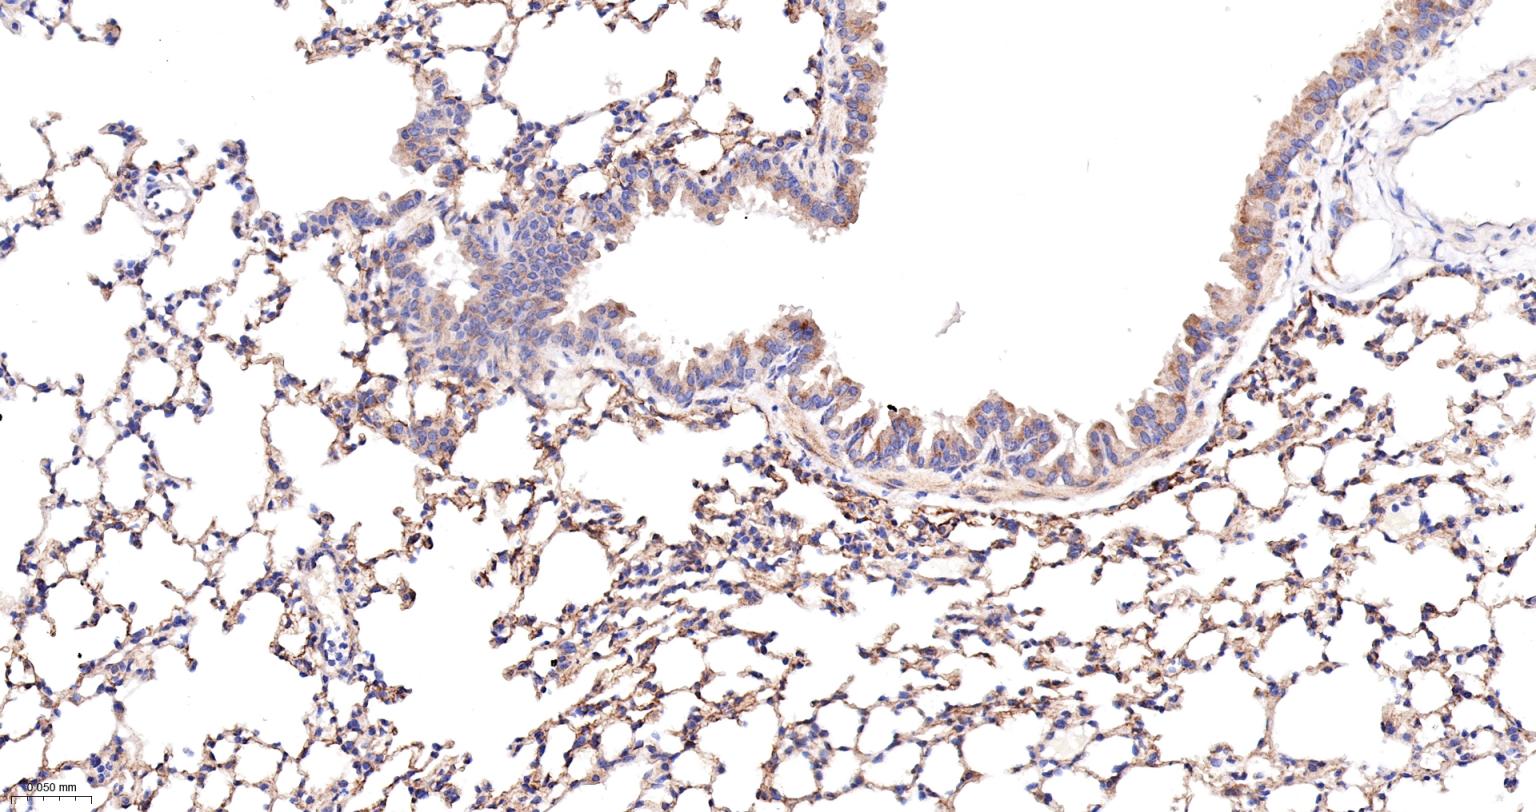

Paraformaldehyde-fixed, paraffin embedded Rat Lung; Antigen retrieval by boiling in sodium citrate buffer (pH6.0) for 15 min; The section was incubated with Radixin Monoclonal Antibody, Unconjugated (bsm-61253R) at 1:200 overnight at 4°C, followed by conjugation to the bs-0295G-HRP and DAB (C-0010) staining.

Paraformaldehyde-fixed, paraffin embedded Mouse Lung; Antigen retrieval by boiling in sodium citrate buffer (pH6.0) for 15 min; The section was incubated with Radixin Monoclonal Antibody, Unconjugated (bsm-61253R) at 1:200 overnight at 4°C, followed by conjugation to the bs-0295G-HRP and DAB (C-0010) staining.